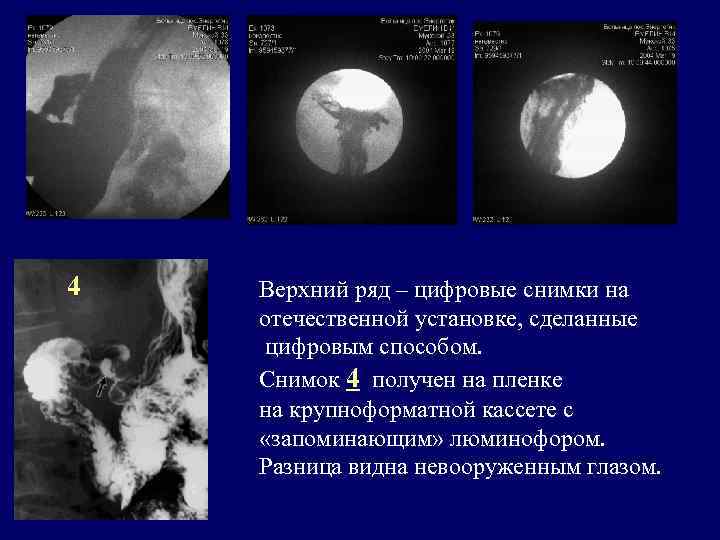

4 Верхний ряд – цифровые снимки на отечественной установке, сделанные цифровым способом. Снимок 4 получен на пленке на крупноформатной кассете с «запоминающим» люминофором. Разница видна невооруженным глазом.